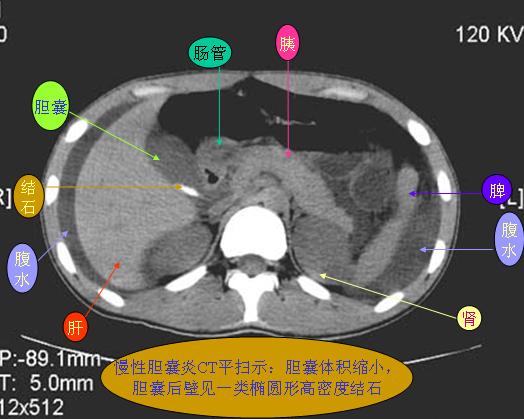

腹部ct解剖与基本病变